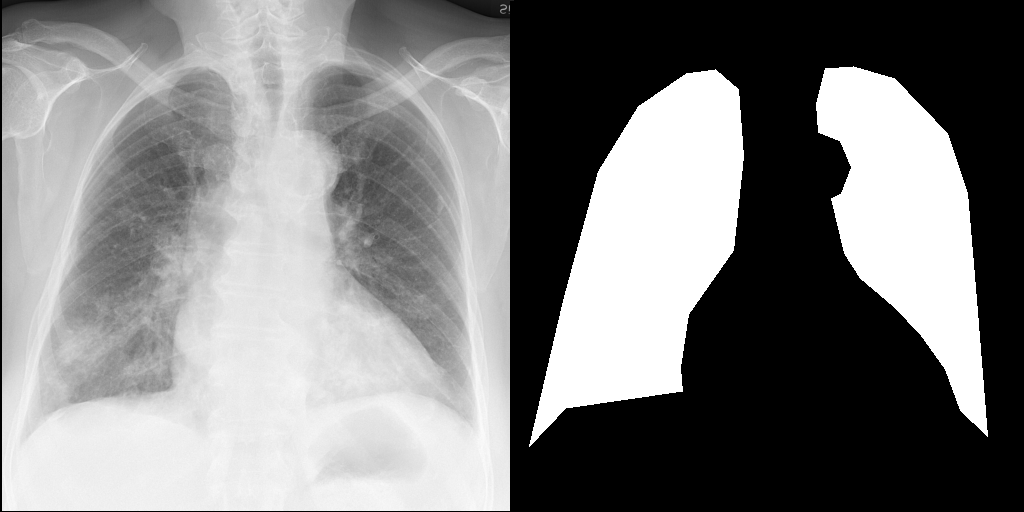

RadEdit Edited Inputs

For this example, we will remove the visual appearance of influence from the lungs, while preventing changes from happening to the rest of the image. To do this, we create a mask of the lung regions and use this as the edit_mask which defines the region we wish the editing prompt to be applied to. Since we want the rest of the image to remain unchanged, we use the inverse as the keep_mask which defines the region where edits are discouraged from taking place.